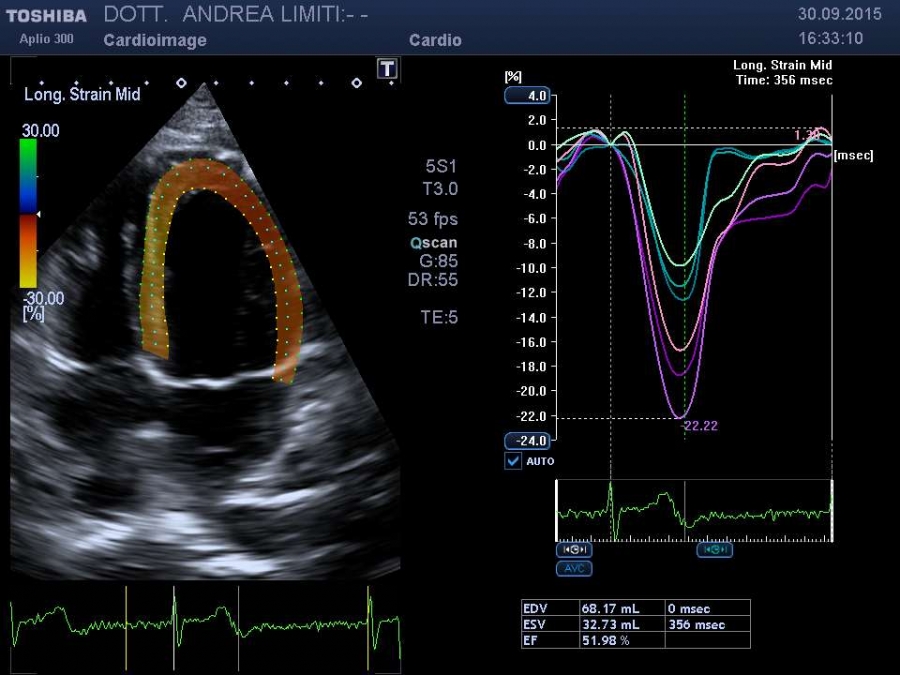

La visita cardiologica, l’Elettrocardiogramma e l’Ecocardiogramma bidimensionale Color Doppler transtoracico consentono di acquisire una ricchezza di informazioni sullo stato anatomico e funzionale del cuore di livello molto elevato che spesso consentono un primo accurato inquadramento dei problemi cardiologici del paziente. E’ importante tuttavia sapere che, anche con gli apparecchi più avanzati, l’ecocardiografia non offre una valutazione diretta dello stato delle coronarie e quindi l’esame non può essere discriminante per la valutazione di sospetti dolori cardiaci.